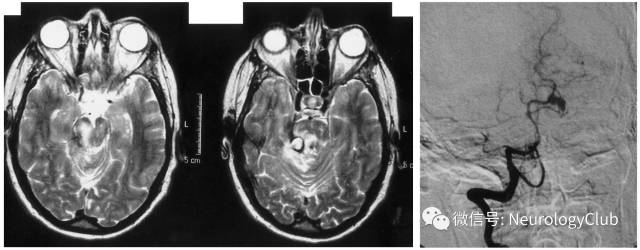

脑动静脉系统受累

(图23:A-B:貌似急性脑梗死的右侧脑桥病灶;C:MRA可见基底动脉中段闭塞;D-E:MRV可见左侧乙状窦和颈内静脉远端以及直窦血栓形成

(图26:头颅MRI可见位于右侧小脑上脚和中脑的动脉瘤,伴脑干弥漫高信号;DSA证实为右侧小脑上动脉动脉瘤)